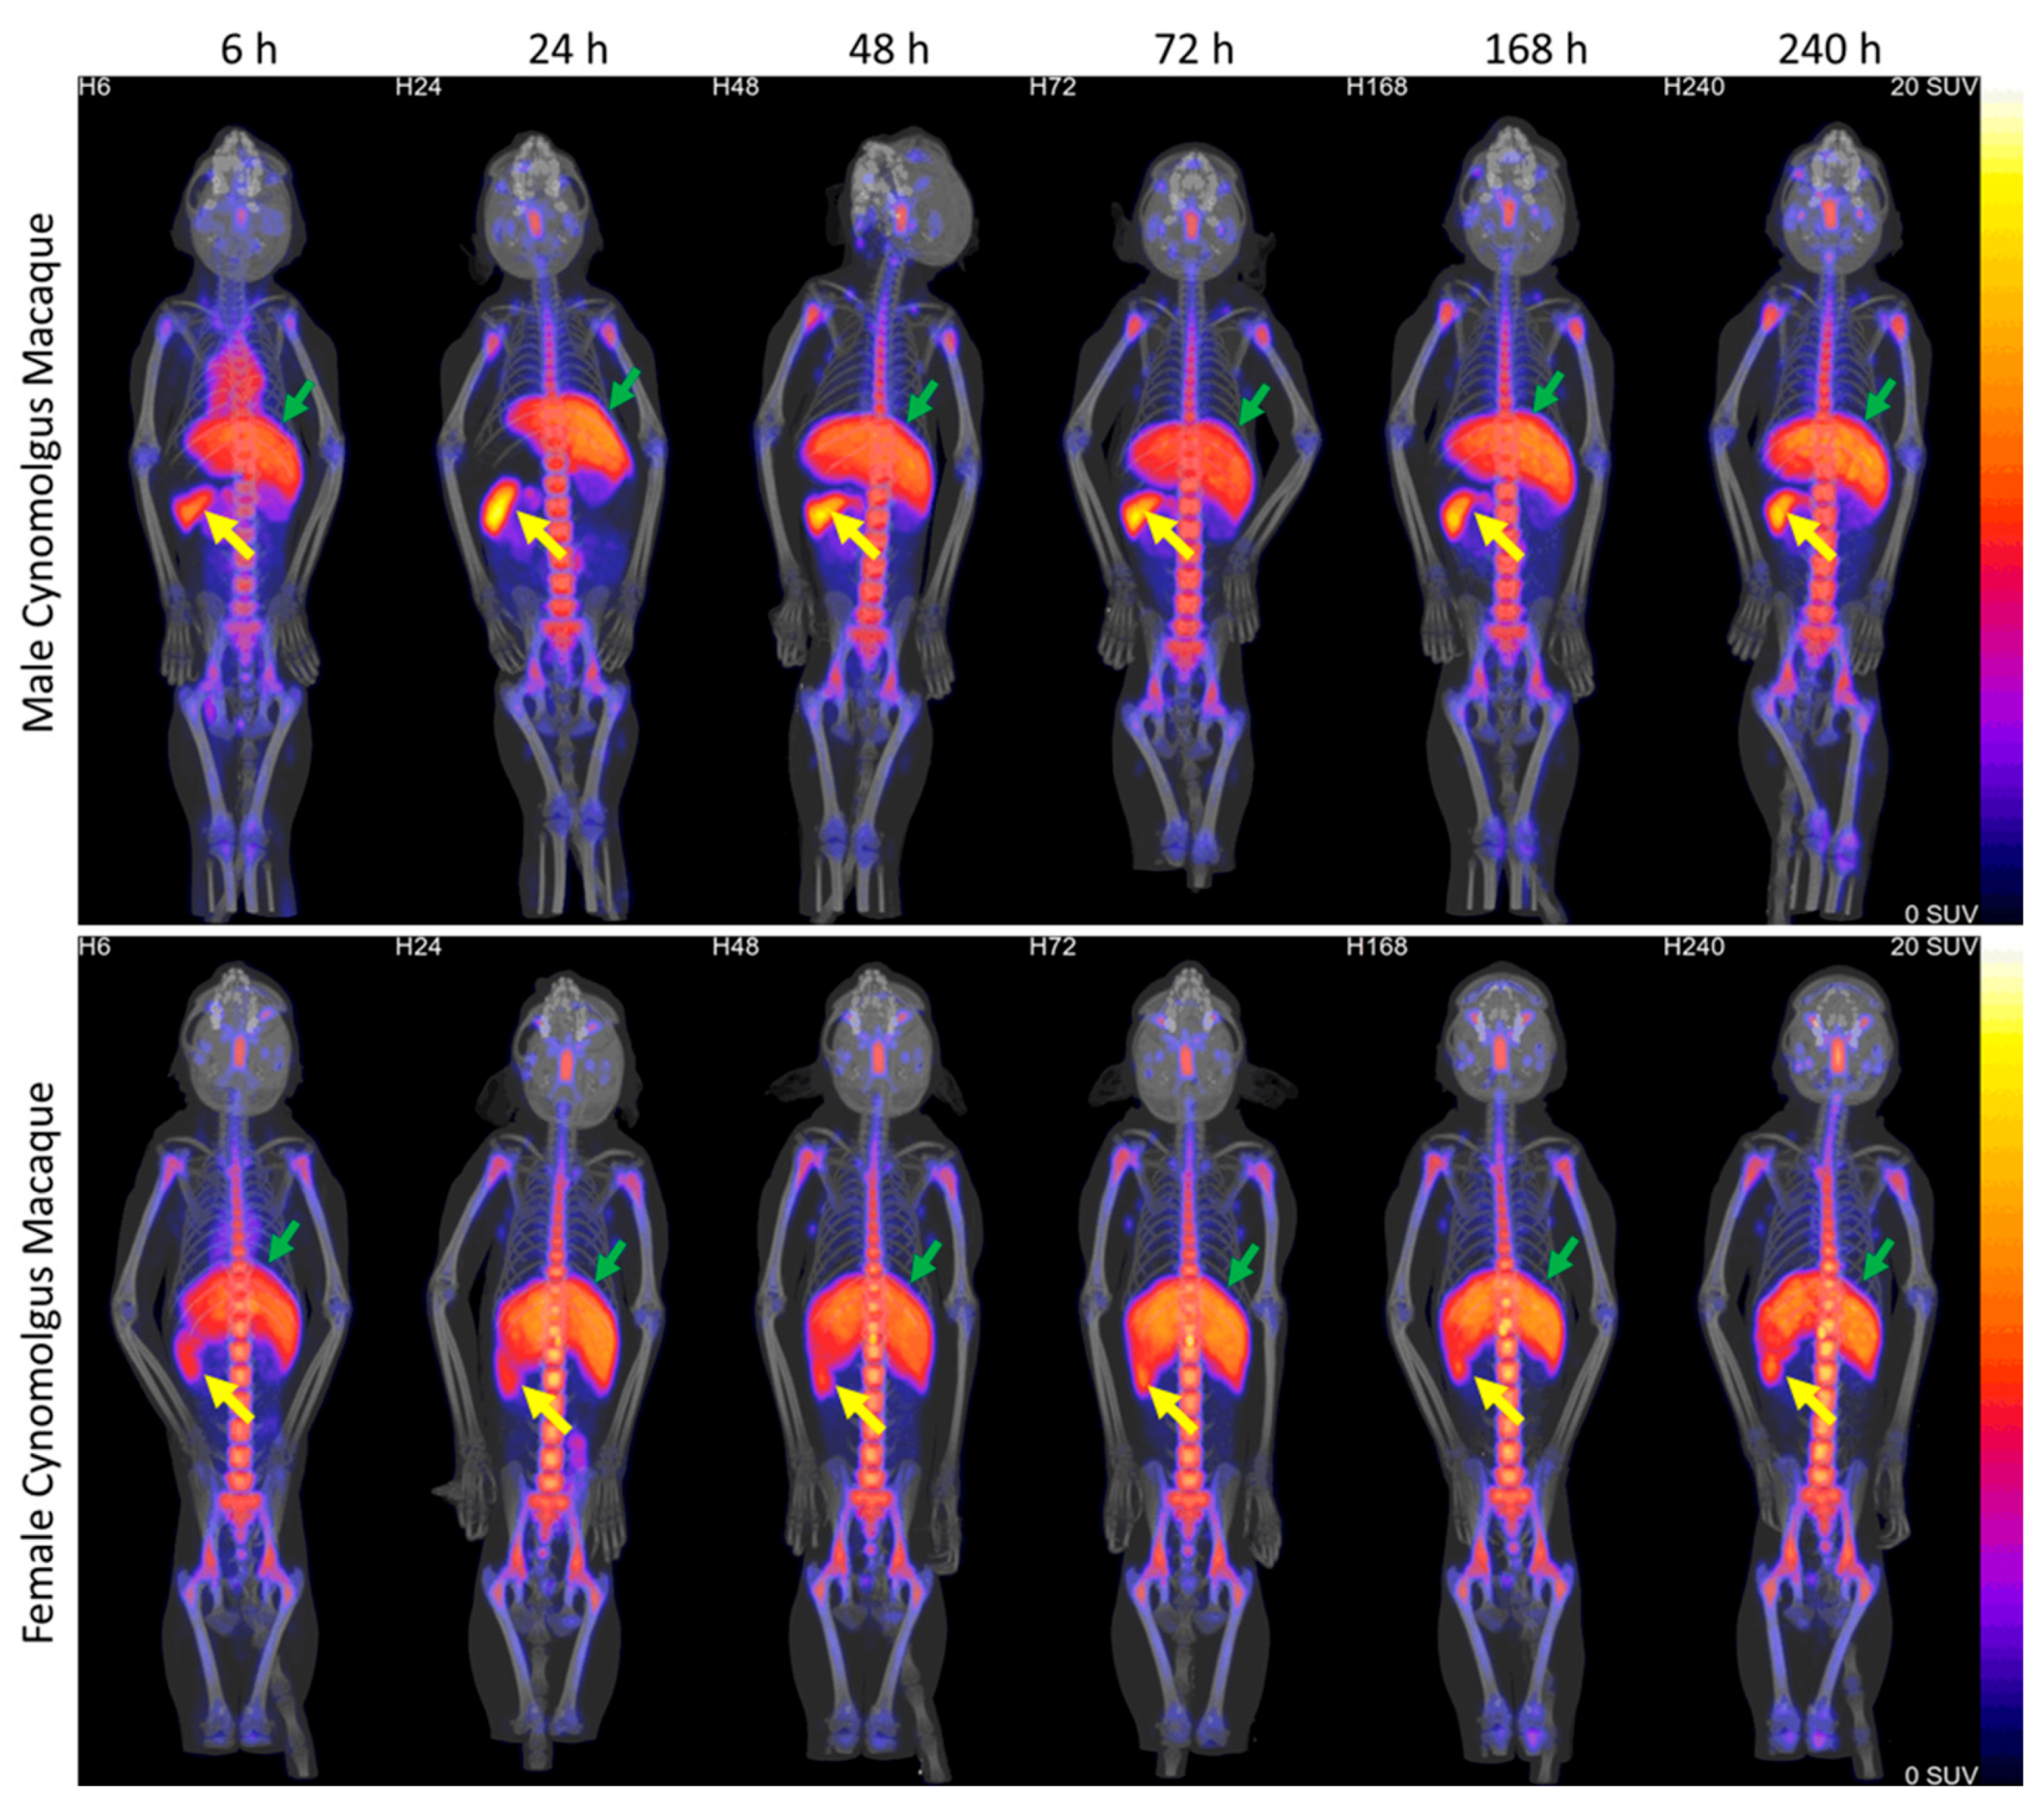

2. Results

- Amato, R.; Gardin, J.F.; Tooze, J.A.; Cline, J.M. Organ Weights in Relation to Age and Sex in Cynomolgus Monkeys (Macaca fascicularis). Toxicol. Pathol. 2022, 50, 574–590. [Google Scholar] [CrossRef]